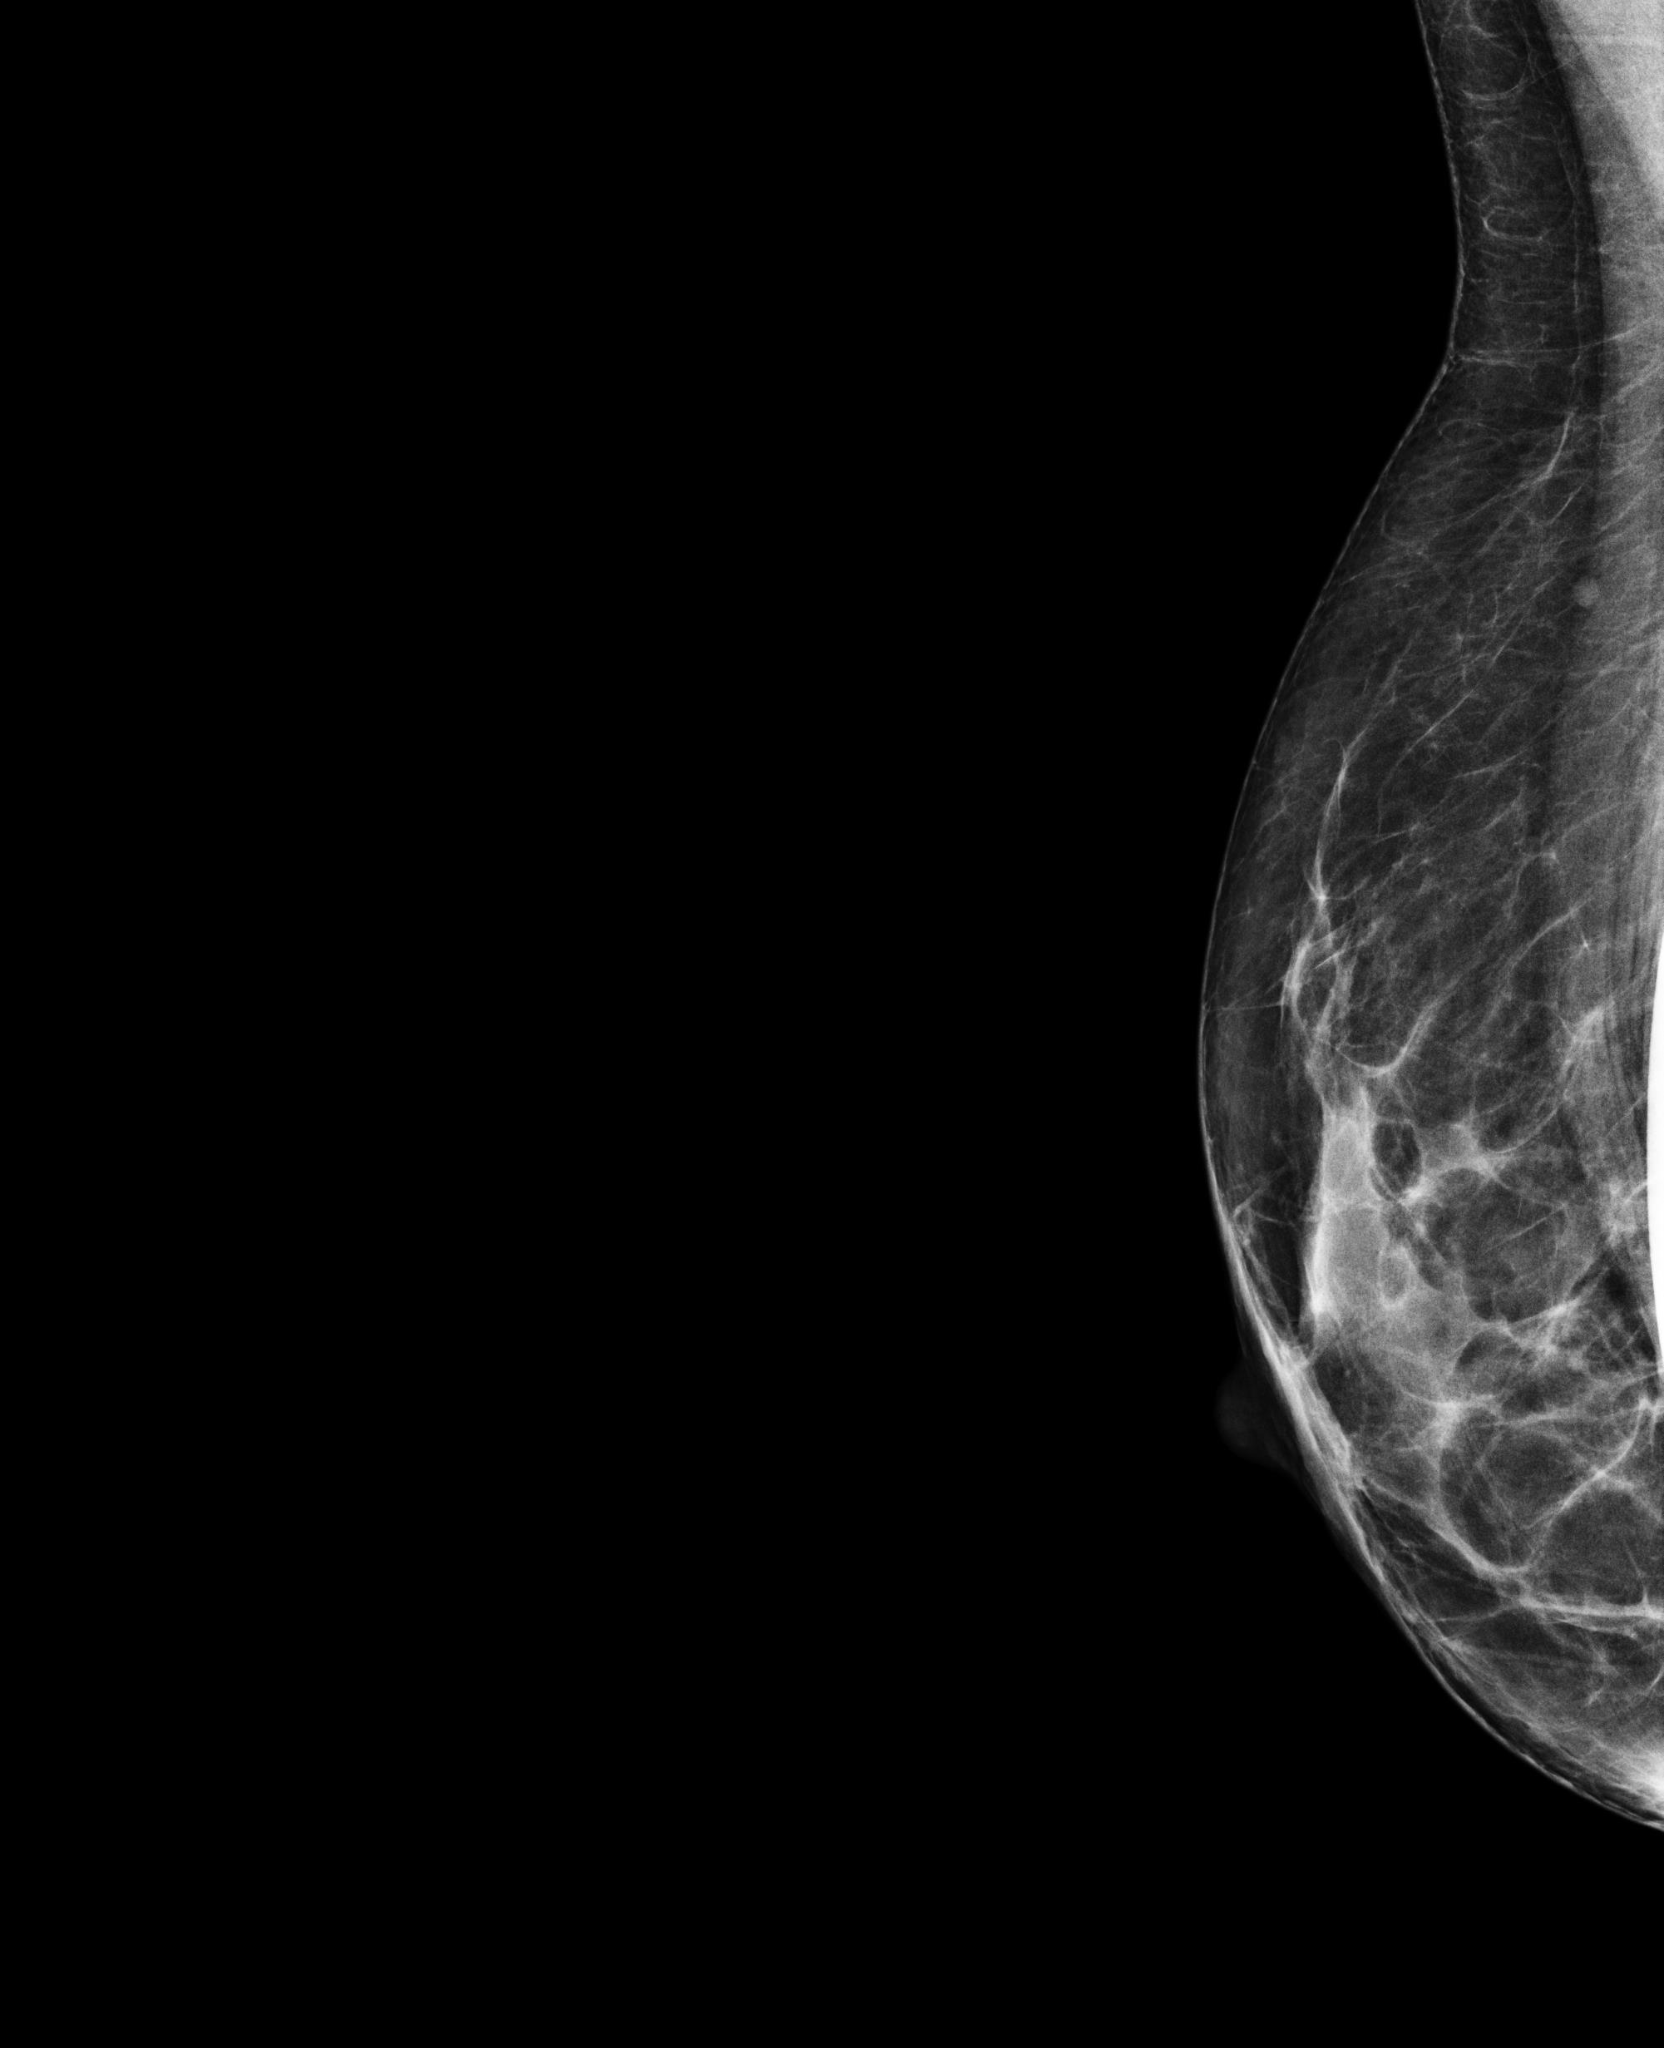

BreastScreen NSW radiographers are trained in taking mammograms for women with breast implants. The pictures below show how special techniques are used to image the breast tissue around implants.